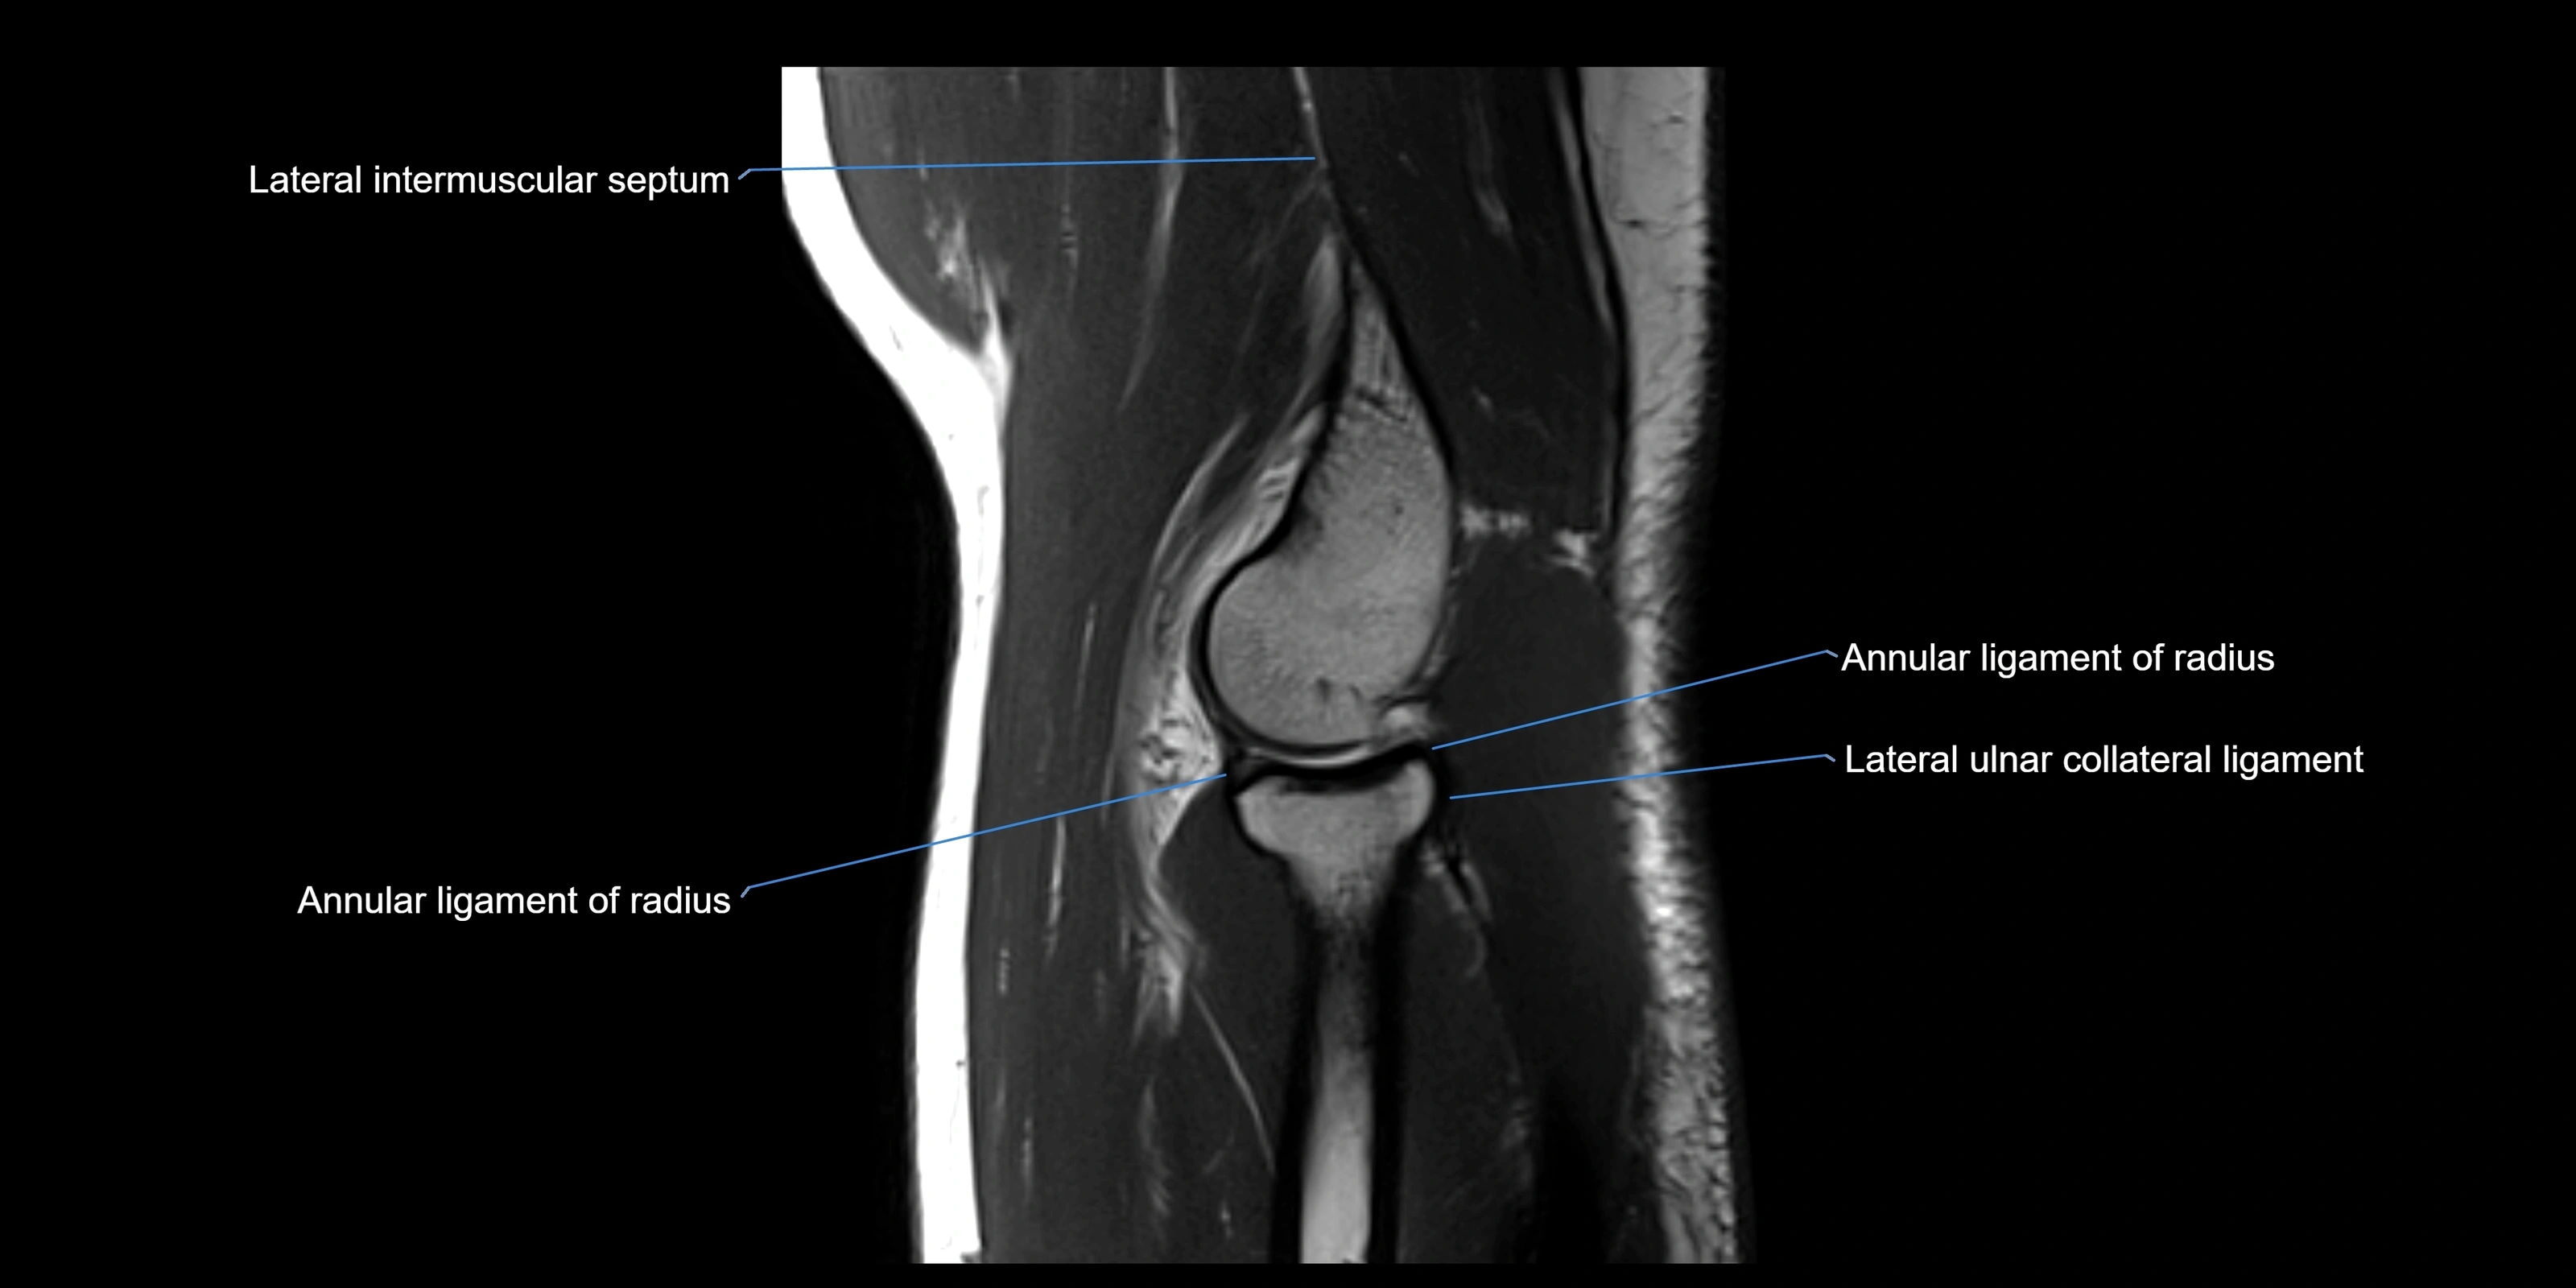

MRI Appearance

T1-weighted images:

• Ligament: low signal intensity (dark), appearing as a continuous band around the radial head.

• Adjacent fat and marrow: bright, creating contrast with the ligament.

• Thickening or disruption indicates injury or fibrosis.

• Joint capsule and synovium seen as thin low-signal lines contiguous with ligament margins.

T2-weighted images:

• Ligament: low signal (dark) with clear delineation from joint fluid.

• Fluid or edema: bright hyperintense, separating or surrounding the ligament in partial tears.

• Complete tear: discontinuity or non-visualization of ligament fibers, often with joint effusion.

MRI images

image